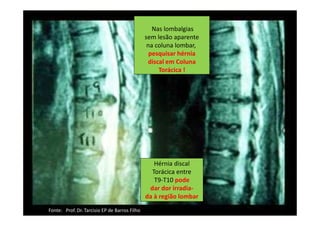

Hérnia Discal Torácica Baixa

PROVOCANDO lombociatalgia =/= Hérnia Discal Lombar

Hérnia discal

Torácica entre

T9-T10 pode

dar dor irradia-

da à região lombar

Nas lombalgias

sem lesão aparente

na coluna lombar,

pesquisar hérnia

discal em Coluna

Torácica !

Fonte: Prof. Dr. Tarcisio EP de Barros Filho